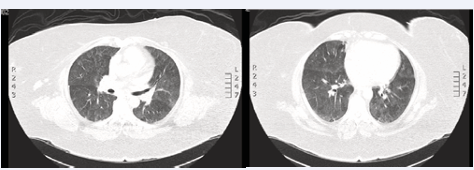

A 52 year-old morbidly obese Hispanic female with a past medial history of hypertension and type 2 diabetes, and no known lung disease to include asthma/atopy, presented with a three day history of new onset dyspnea at rest, non-productive cough, and fatigue. Patient denied fevers, sick contacts, and had no recent travel. She was a lifetime non-smoker with no environmental or occupational pulmonary exposures. The patient started extended-release Exenatide injections three weeks ago and had an erythematous, pruritic reaction at the injection site with each prior injection that would last for days. Other medications included metformin, atorvastatin and lisinopril. Vital signs on presentation showed a blood pressure of 143/88, a heart rate of 81, and a temperature of 98.1°F. ABG showed a pH of 7.43, pCO2 of38, and a paO2 of 67 while on aFiO2 of 36%. Physical exam was notable for diffuse bilateral end-inspiratory rales, no lower extremity edema, and resolution ofher previous rash at the site of her injections. Initial blood-work and urinalysis were only notable for a leukocytosis of 13,790 with 7.5% eosinophils (1,034 absolute eosinophils), a mildly elevated D-Dimer of 0.87 mcg/ml (ref range 0-0.43), procalcitonin of <0.05 (reference range <.5), and a negative respiratory virus panel PCR. HerESR was elevated at 42 mm/hr (normal 0-30) and her C-Reactive Protein was increased to7.5 mg/dl (normal 0-0.49). Serologies for connective tissue diseases were negative. Her ANCA was negative. Serologies for systemic fungal infections were negative. Normal Pro-BNP of 102 pg/ml (normal 0-125) and normal troponin T < 0.01 ng/ml with her electrocardiogram showing normal sinus rhythm with no evidence of ischemia or right ventricle strain. Computed to mography (CT) pulmonary angiogram was negative for pulmonary embolism. Her high-resolution computed tomography (HRCT) showed diffuse bilateral ground-glass opacities with areas of mosaic attenuation and no mediastinal lymphadenopathy. Transthoracic echocardiogram was normal with a left ventricular ejection fraction of 65%, normal left ventricular diastolic function, and no significant valvular disease.

The patient’s symptoms intensified and hypoxemia worsened within 48 hours of admission which subsequently required humidified high flow nasal cannula to maintain her SpO2 saturations above 92%. Bronchoscopy with BAL was performed which showed a cell differential of 40% eosinophils, 45% macrophages and 15% lymphocytes. Bacterial, fungal, and AFB cultures were all negative. Viral PCR, herpes simplex virus antigen, and galactomannan antigen were also negative. Cytology demonstrated no evidence of malignancy (Figure 1,2).

Figure 1 HRCT showing diffuse bilateral ground-glass and patchy airspace opacities with areas of mosaic attenuation.

Chest radiography and HRCT are key component for the evaluation of ELDs. HRCT abnormalities can vary based on etiology of ELD but often show ground glass opacities, diffuse reticular opacities, varying degrees of bronchiectas is or airway inflammation, and/or consolidations [2]. The pattern seen on imaging may guide clinicians towards an etiology for a patient’s ELD, have help guide a bronchoscopic evaluation, and is ultimately valuable for monitoring patient’s response to therapy.